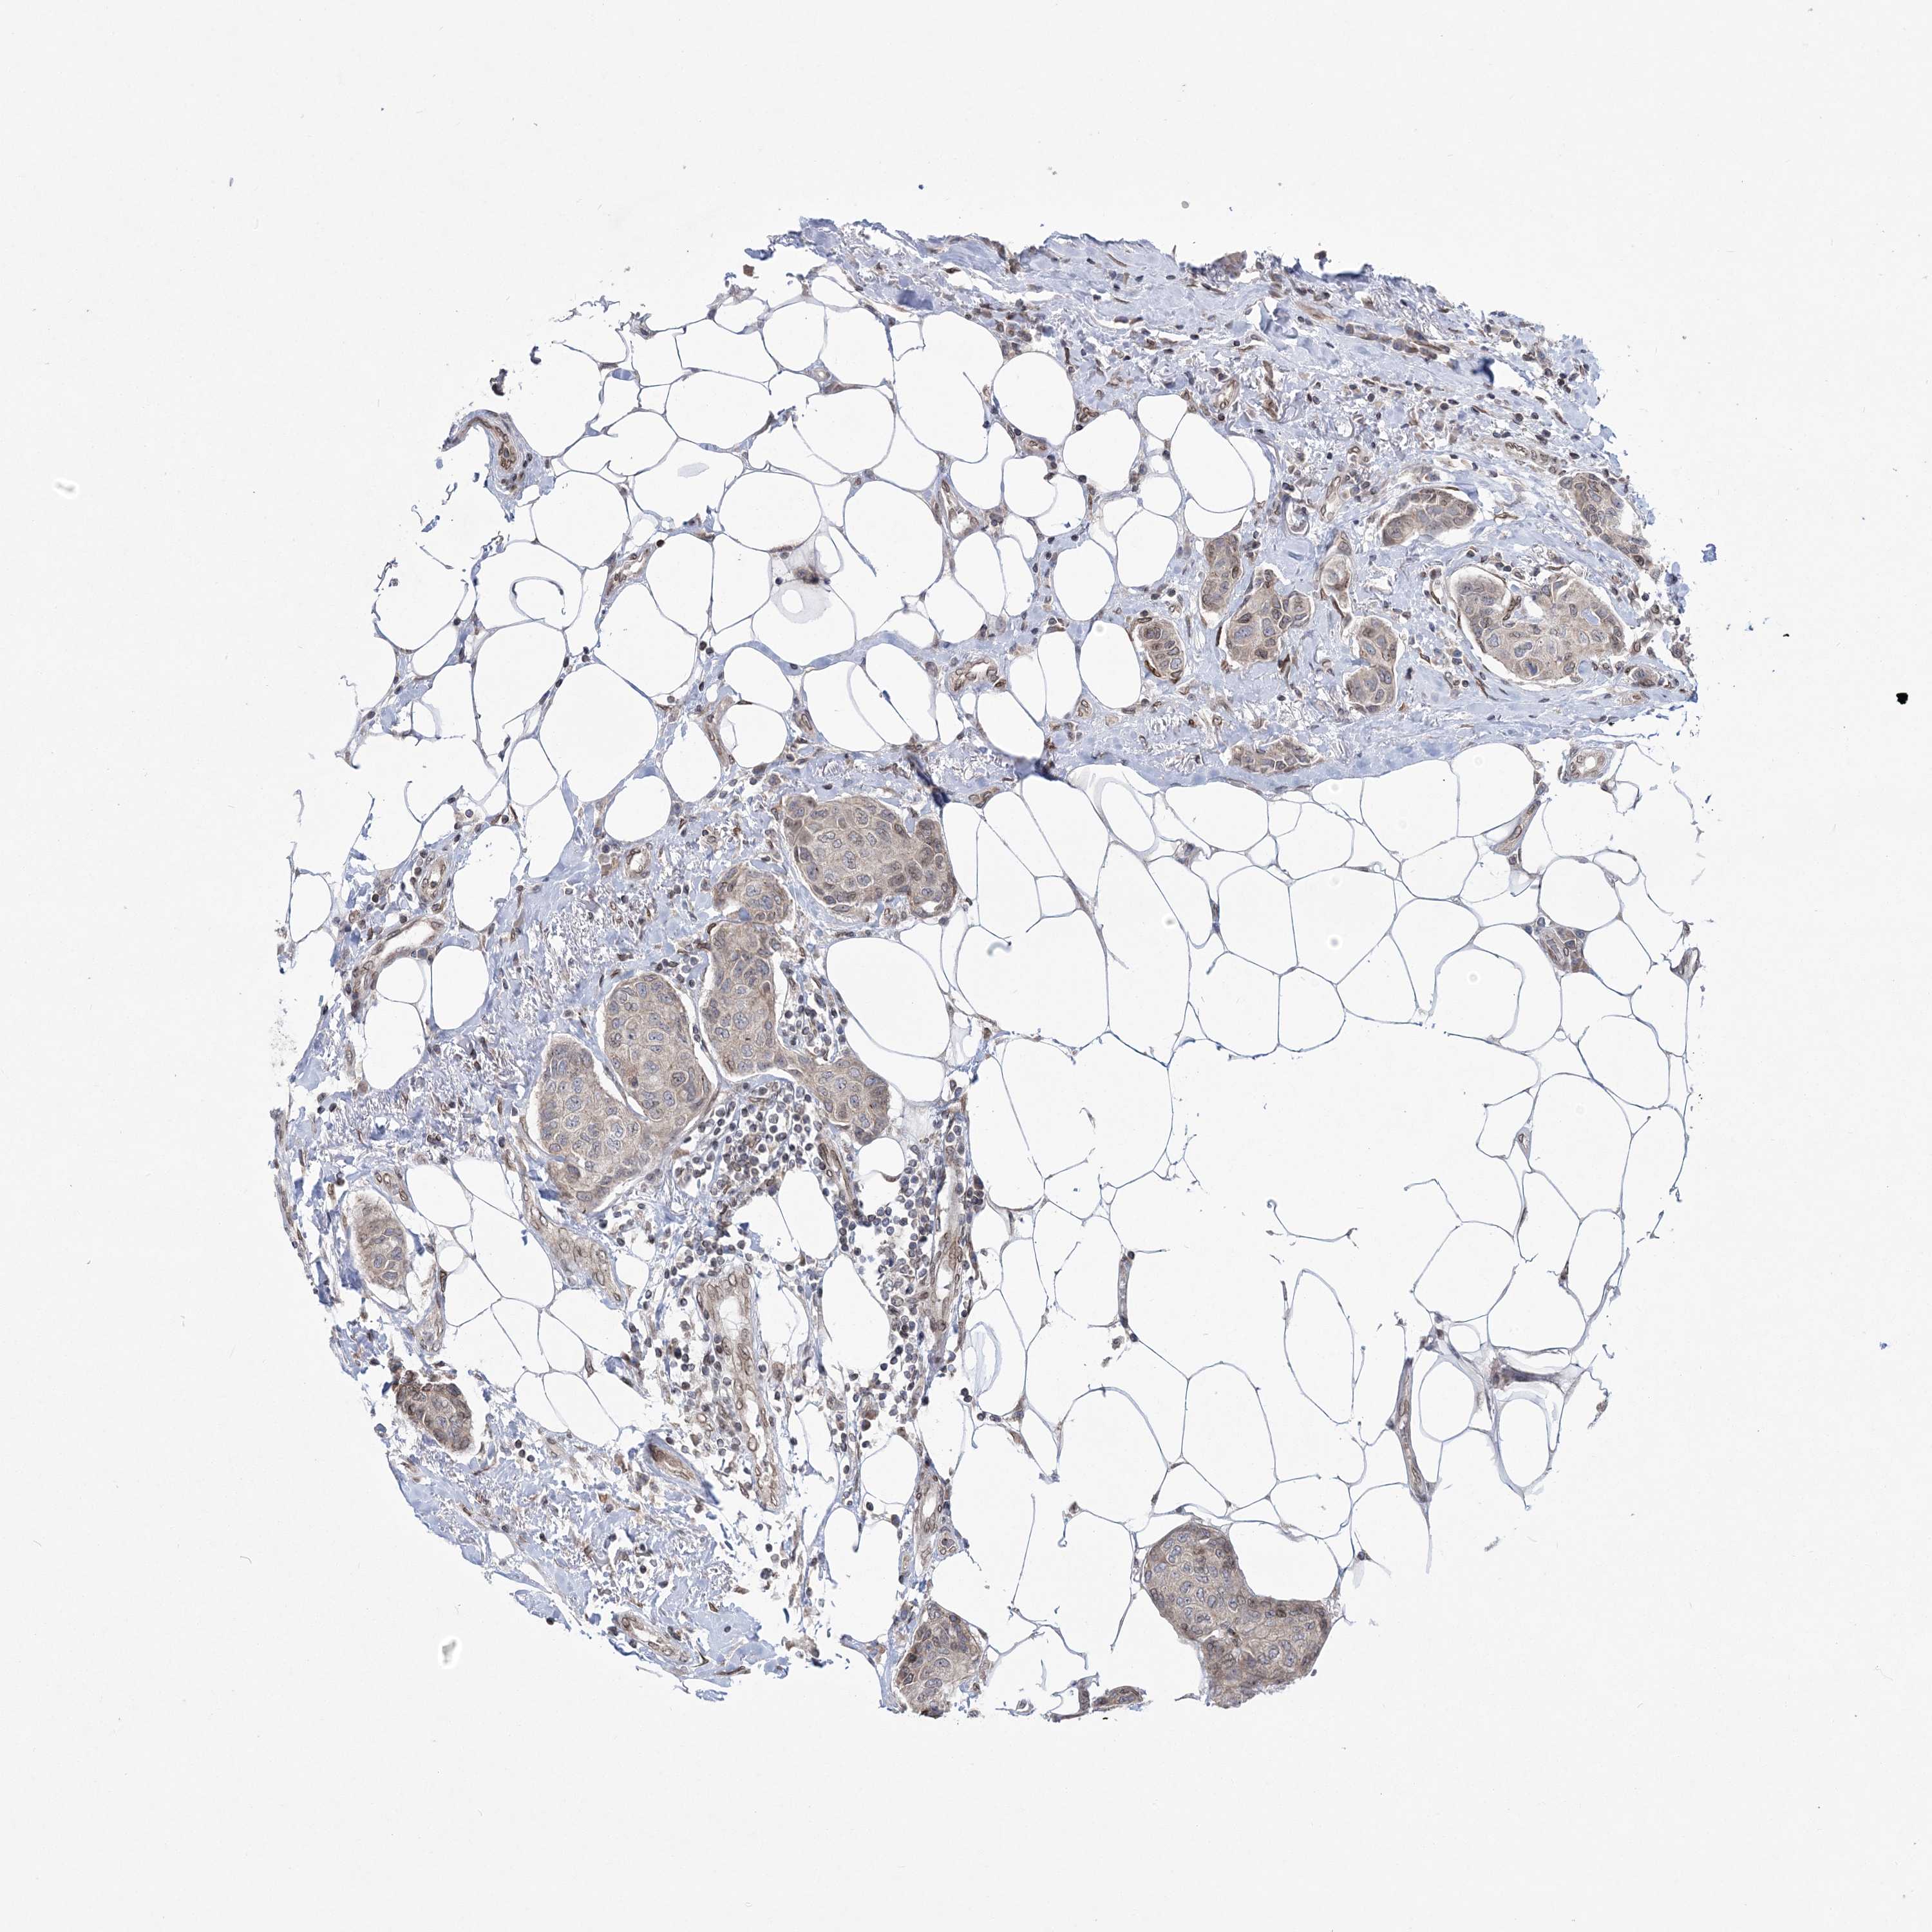

CANCER BREAST CANCER Show tissue menu

BRCA TCGA BRCA VALIDATION PROTEIN EXPRESSION